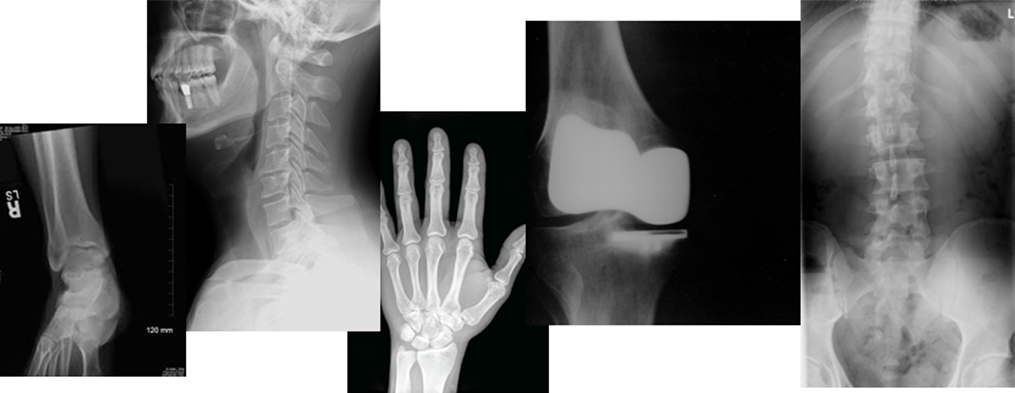

엑스레이 검사

주로 뼈의 이상을 확인하며 골절, 탈구, 염좌 등을 진단합니다